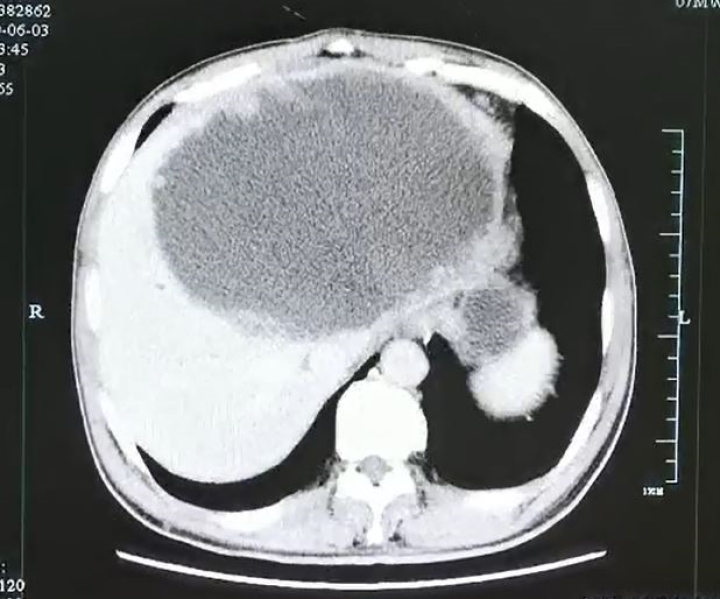

这一检查可把医生和谢师傅都吓坏了,

因为超声影像科检查显示

谢师傅的左肝已经被“掏空”了,

变成了一个大脓球

医生仔细测量了一下,

大脓球达到19cm×18cm×12cm 大小。

入院后腹部CT检查发现肝脓肿壁上长了很多肿瘤样的结构,而且壁很厚看来这个肝脓肿不简单。

经过三周的引流和保守治疗,复查增强CT发现谢师傅左肝的脓肿小了一大半,但是肝脓肿厚壁及厚壁上的很多肿瘤样组织没有变化,引流管里引流出来的液体开始减少,而且脓腔也不再进一步缩小,显示出这个脓肿很难自愈。